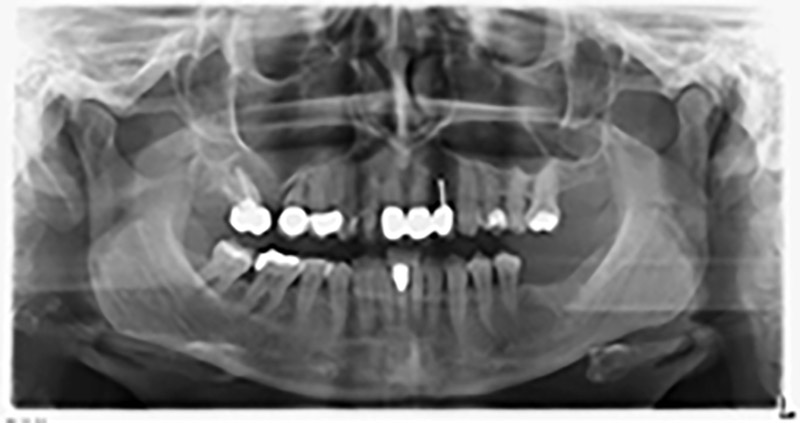

La paciente de 59 años presentaba una periodontitis avanzada, describía una desagradable sensación y un mal gusto proveniente del primer cuadrante. La evaluación clínica mostró en general marcadas profundidades de bolsa y una degeneración ósea muy avanzada en las regiones 16 y 14. El estudio radiológico corroboró estos resultados (figura 1). Las piezas dentales 16 y 14 no podían conservarse.